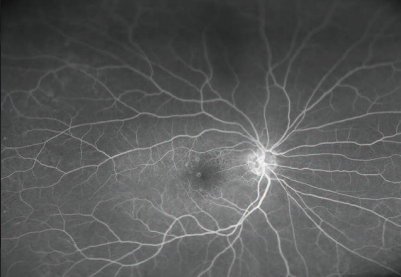

optomap fa images demonstrating excellent detail of the central macula in dry AMD (magnified images).

This case study captured by the Optos ultra-widefield digital imagingdevice demonstrates the benefits offered by the technology. Duke University photographers were able to acquire a clear image set through relatively dense cataracts; something that is always a challenge with traditional mydriatic white-light based cameras. The red/green laser allows for less scatter as the beams enter the anterior segment allowing for a better image of the retinal surface.

The ultra-widefield image illustrates AMD changes affecting both the central and peripheral retina. Recent studies have demonstrated the peripheral retinal findings in early AMD, and this may be an important predictive phenotypic marker for outcomes.